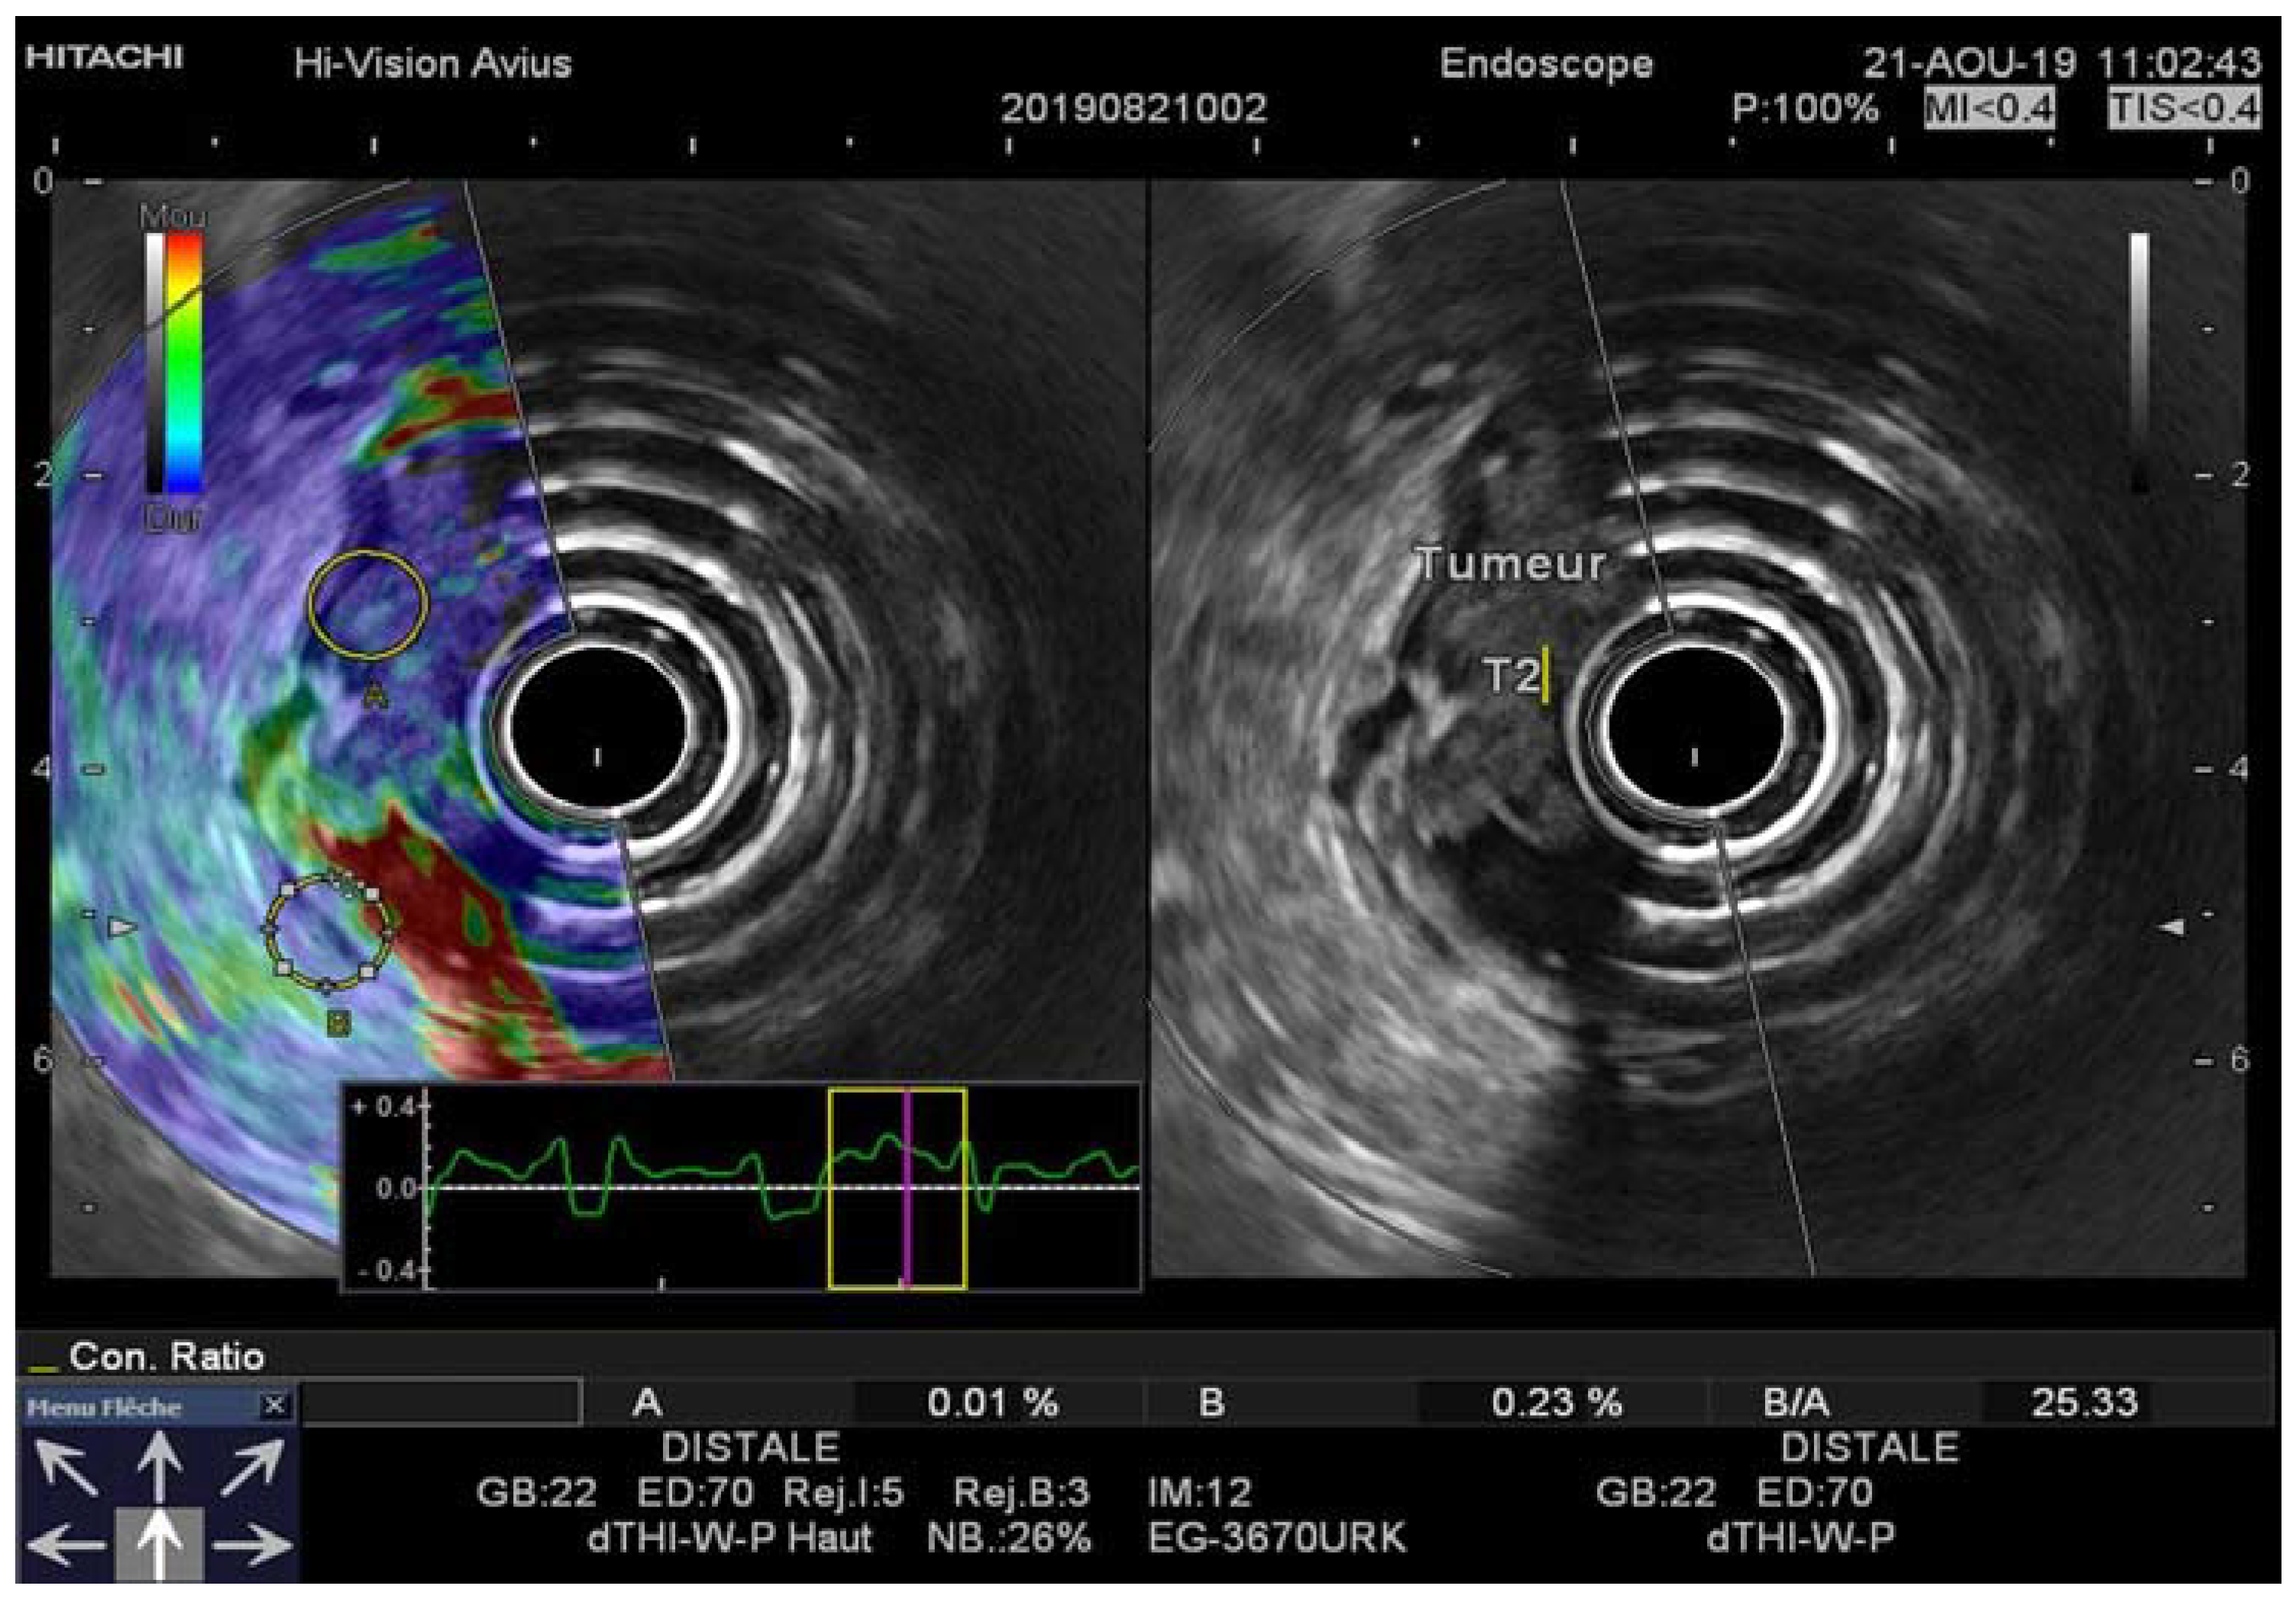

Figure 4. Images of a 60-year-old man with pT2N1 rectal cancer. Regions of interest for the EUS-RTE measurements were placed on a suspicious lymph node (A) and the normal portion of the rectal wall (B), superimposed on the B-mode image. RTE, real-time elastography.